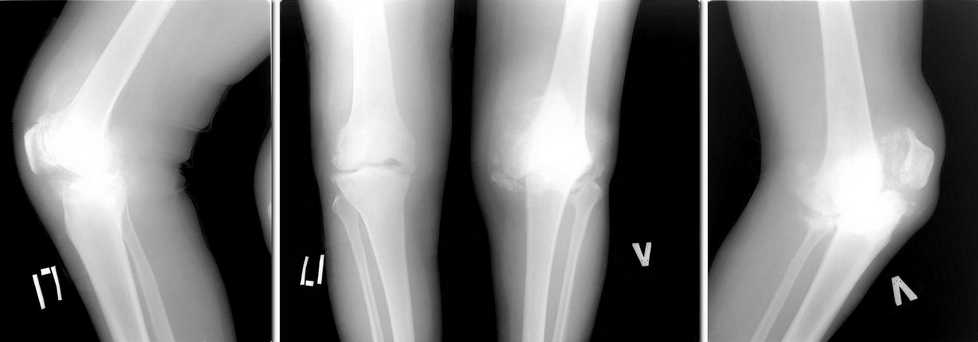

1,5 года назад установлен диагноз: Нейросифилис. Находится на диспансерном наблюдении у венеролога. Обследован онкологом, фтизиатром - "своей" патологии не находят. Бакпосев синовиальной жидкости - нет роста. Боли в коленях постоянные. Ходить может. Разгибание полное, сгибание 90*. На представленных рентгенограммах в сравнении с предыдущими, 2 месячной давности (в настоящее время не располагаю), добавился патологический перелом медиального мыщелка левого бедра. Природа артроза не ясна, однако, умозрительно - нейросифилис.

Дилемма такова: 1)Эндопротезирование? но беспокоит вопрос о стабильности компонентов протеза в будущем, а следовательно и целесообразности деяния. 2)Артродезирование? - состоится ли артродез на фоне продолжающегося разрушения костей. Обе операции технически вполне выполнимы. И последнее - следует ли оперировать. Заранее спасибо за добрые советы.